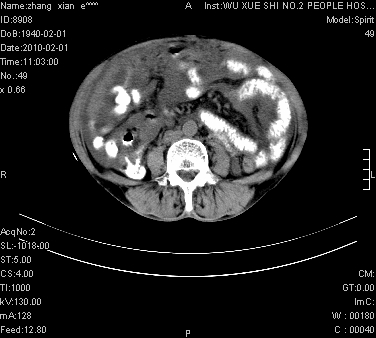

标题: CT24434:70岁 女 腹胀,腹水原因待查 [打印本页]

大量腹水,脾脏囊性占位,子宫颈占位,右侧腹股沟淋巴结肿大,建议+c,先查妇科。

腹盆腔大量积液,子宫增大,子宫颈增大外形不规则,内见低密度影,膀胱后壁显示不清,右腹股沟肿大淋巴结,脾脏囊性占位,子宫颈占位,子宫颈癌?建议增强。

考虑:1、腹膜转移,大量腹水;

2、脾占位性病变;

3、左侧卵巢占位性病变,建议增强进一步检查。